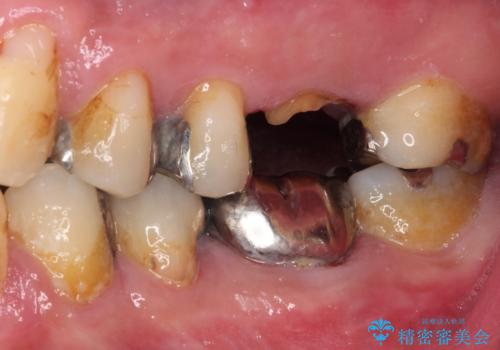

- 根っこの一部だけになった歯と咬むと痛みのある歯を気にして来院された患者様です。

上顎の歯根のみとなった歯は抜歯が必要であったので、抜歯を行い、インプラントあるいはブリッジのよる補綴治療を提案しました。

前後の歯は銀歯が装着されていたため、ブリッジによる補綴治療として、前後の歯もセラミックに置き換えることとしました。

歯根のみとなっていた上顎の歯は、そのうち治療すれば残せるであろうと思っていたようですが、どこの歯医者に相談しても抜歯と言われたため、抜歯することとしたようです。

むし歯は放置して改善することはあり得ませんので、早めの処置が大切です。